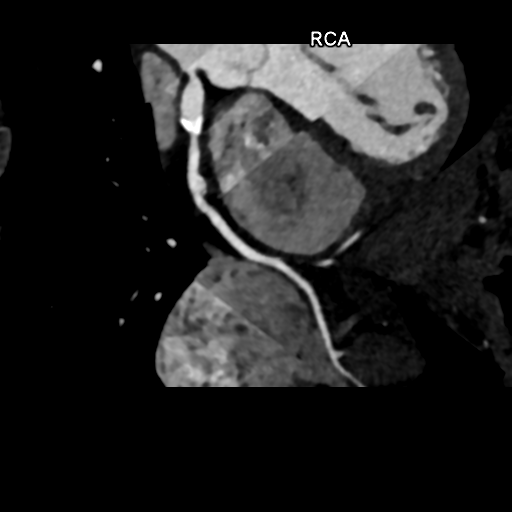

Anomalous origin of both coronary arteries from left sinus of Valsalva

RCA is ectopic

Axial MIP image shows common origin of RCA and left main coronary artery from left aortic sinus. Anomalous inter-arterial course of RCA between aorta (AO) and pulmonary artery (PA).

Right Coronary Artery (RCA): 2 fusiform aneurysms without thrombosis- 1) proximal segment 15 mm long and 8 mm in diameter with mural calcification and 2) mid segment 7 mm long and 6.5 mm in diameter at the origin of a small AM branch.